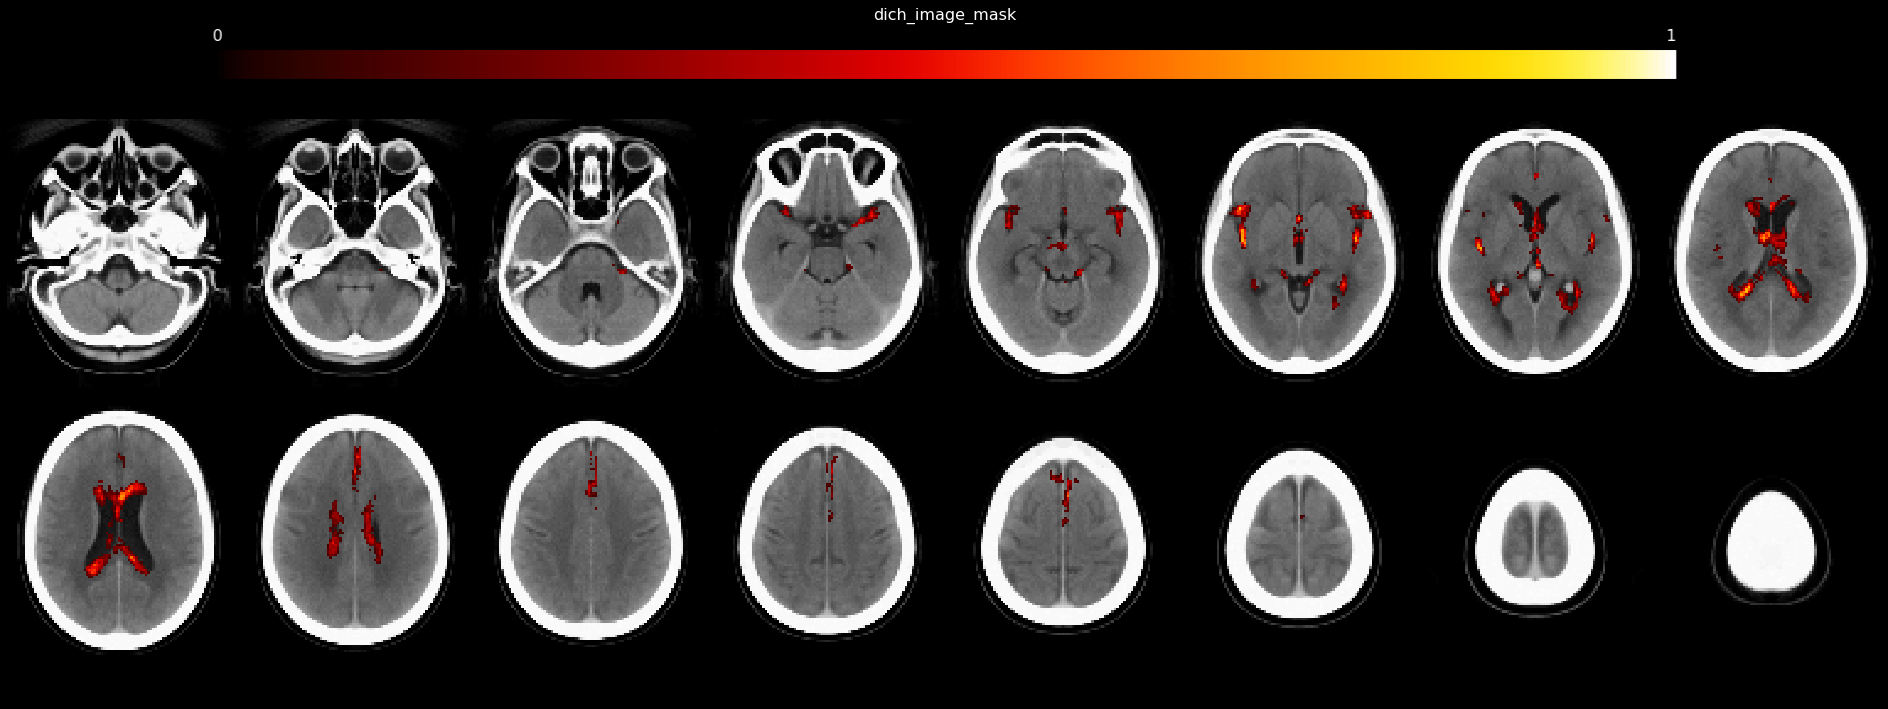

Patients with LVO from four hospitals in Europe and the USA were included. Three cohorts were used as a derivation cohort, and the fourth served for validation. Presenting CT imaging was processed using Brainomix in-house software to automatically localize and quantify atrophy (frailty-index). Masks from the derivation cohort were used to localize regions of atrophy significantly associated with poorer functional outcome (modified Ranking Scale 3-6) using a voxel-based, multivariate method (Sparse Canonical-Correlation-Analysis) (see Figure 1). For both derivation and validation cohorts, the degrees of overlap between each patient’s atrophy mask and the regions associated at a group level with poor outcome were calculated. This was used as an independent predictor of functional outcome in multivariate analysis adjusting for overall brain frailty-index, recanalization status, and ASPECT score

The derivation cohort consisted of 658 patients (mean age 69.6±15.0, median ASPECTS 9 [7-10]), while the validation cohort consisted of 447 patients (mean age 64.7 ±15.5, median ASPECTS 8 [5-10] ). Atrophy localized to the lateral ventricles and sylvian fissure was significantly associated with poorer outcomes (Figure 1). In both derivation and validation cohort, the presence of this spatial pattern of brain frailty (quantified using the degree of overlap) was an independent predictor of poor functional outcome (Table 1).